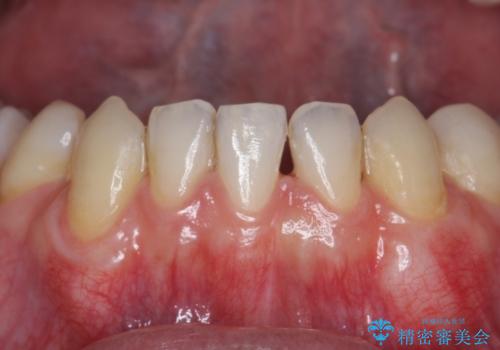

- 下の犬歯の歯茎の下がりを気にされていました。

矯正治療予定であったので、矯正治療前に歯茎の移植を行い、さらに退縮するのを防ぎました。

下がったのを元に戻すことは必ずしもできないですが、厚みを増やして下がりにくくすることはできます。今回左下の犬歯は特に、しっかり下がったのも元に戻すことができ、大変うまくいきました。